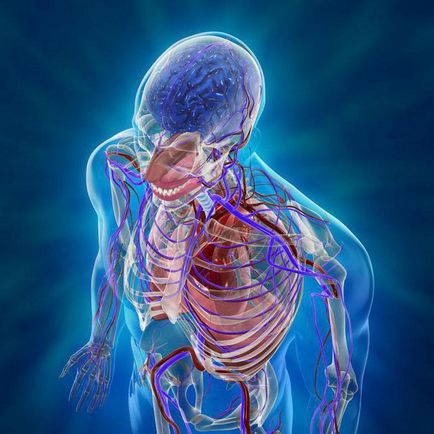

Az emberi test - egy organizmus, ahol az intézkedés az összes szervek és rendszerek szorosan összefügg. Az alapvető egység a sejt. Mire elérik a felnőttkort emberi test egy átlagosan három milliárd sejt. Mindegyikük alakított szervek, beolvadt a rendszer, amelyek mindegyike fontos szerepet játszik az életben. Rendszerek az emberi test:

- Szív- és érrendszer. Ez magában foglalja a kapillárisok, artériákat, vénákat szív. A fő funkciója a rendszer vért pumpál, elküldi az összes szerveket. A bal oldala a szív - „pumpa” az egész test, a jobb oldalán a szívizom szállít vért a tüdőbe gazdagítása érdekében, hogy oxigénnel. A szív három rétegből (szívizom, epicardiumban, szívbelhártya). Mindegyikük rendelkezik egy eltérő sűrűségű és a funkcionalitás.

- Izomrendszer. Ez áll az emberi csontváz, amelyben a csontok egy vonalban vannak egymással ízületek által támogatott izmok kapcsolódnak a vázhoz inak. A tanulmány az emberi test gyakran kezdődik vizsgálata a vázszerkezet. Általában, a csontváz áll 206 csontok.

- Az idegrendszer. Az idegrendszer hordozza a szervezet felelős információt a test és a környezet. Osztva perifériás és centrális.